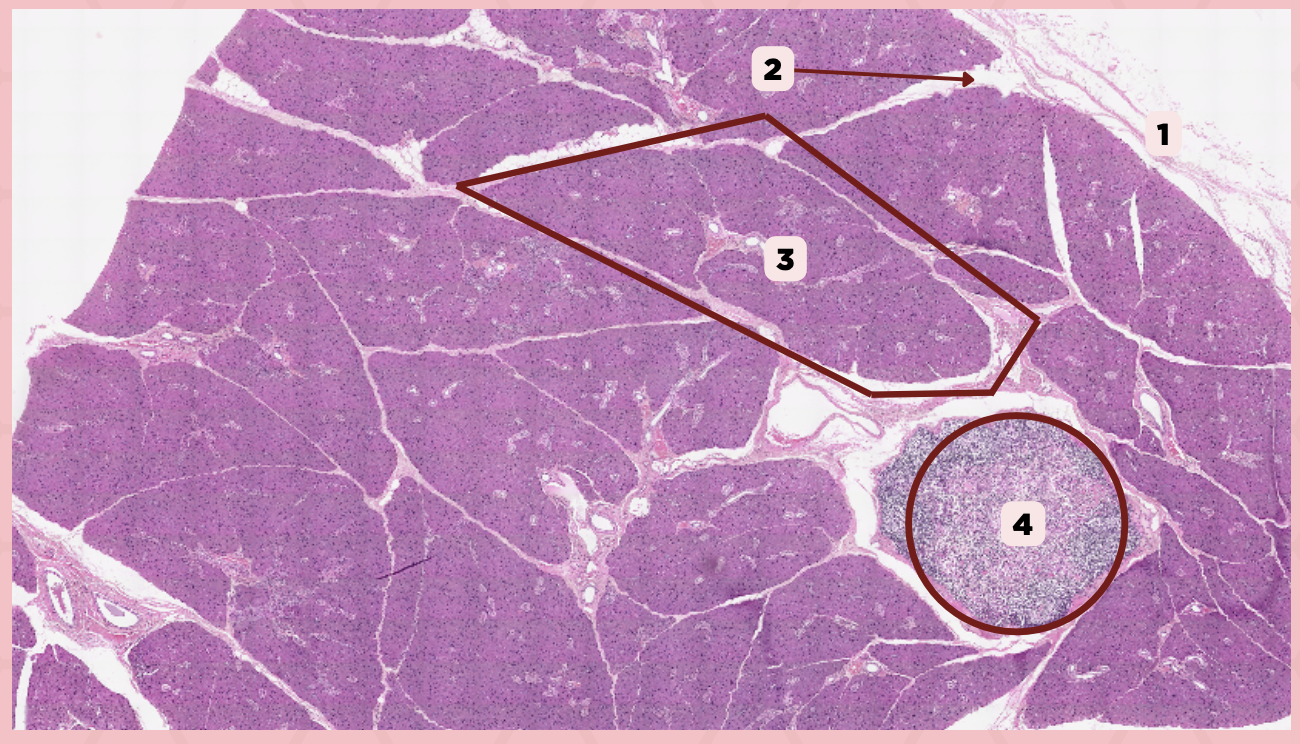

Parotid

Identify the specimen.

Capsule

Identify the structure labeled as 1.

Lobule

Identify the structure labeled as 2.

Lobe

Identify the structure labeled as 3.

Connective Tissue

Identify the structure labeled as 4.